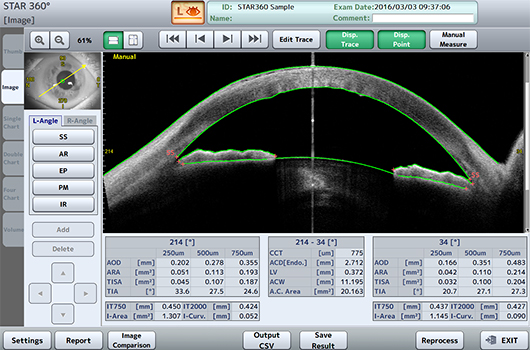

W aplikacji STAR 360°, CASIA2, dzięki automatycznemu wykrywaniu ostrogi twardówki mierzy kąt przesaczania na pełnym obwodzie przedniego segmentu, co zapewnia szczegółowe parametry umożliwiające perfekcyjną diagnostykę jaskry.

Nie tylko mierzy, ale także wyświetla wynik na szczegółowym wykresie/mapie graficznej. Wykresy można wybierać spośród wszystkich wartości pomiarowych w zależności od własnych potrzeb.